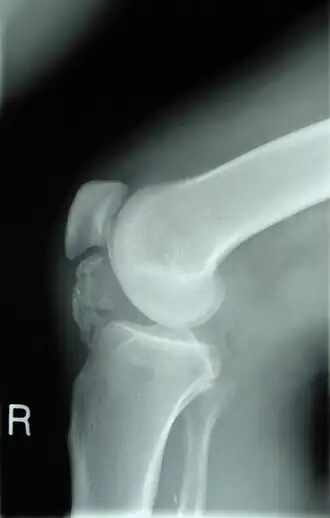

![]() Radiografía lateral de una rodilla que muestra la osificación de los tejidos peritendinosos en un paciente con osteocondroma. | ||

Un osteocondroma es un tipo de tumor benigno compuesto de elementos óseos y cartilaginosos.[1][2] Está constituido por excrecencias óseas recubiertas por cartílago, que se forman únicamente en la metáfisis de los huesos de origen endocondral. Es la neoplasia más frecuentemente observada en el esqueleto.

Un osteocondroma es un tumor benigno que contiene hueso y cartílago, y aparece generalmente cerca del extremo de un hueso largo. Este tumor, uno de los tumores óseos benignos más comunes, toma la forma de un cartílago que encapsula un espolón óseo o excrecencia en la superficie del hueso, por lo que también se le denomina exostosis osteocartilaginosa. Cuando una lesión ósea exofítica contiene una cubierta cartilaginosa mayor de un centímetro de altura, o si se asocia a dolor, no se piensa que es un riesgo más alto de la lesión que representa un condrosarcoma.

Los osteocondromas se diagnostican y se supervisan mediante el uso de radiología. Generalmente los tumores crecen hacia el exterior en las piernas o en los brazos, sin embargo, muy pocos casos crecen hacia el interior del hueso.